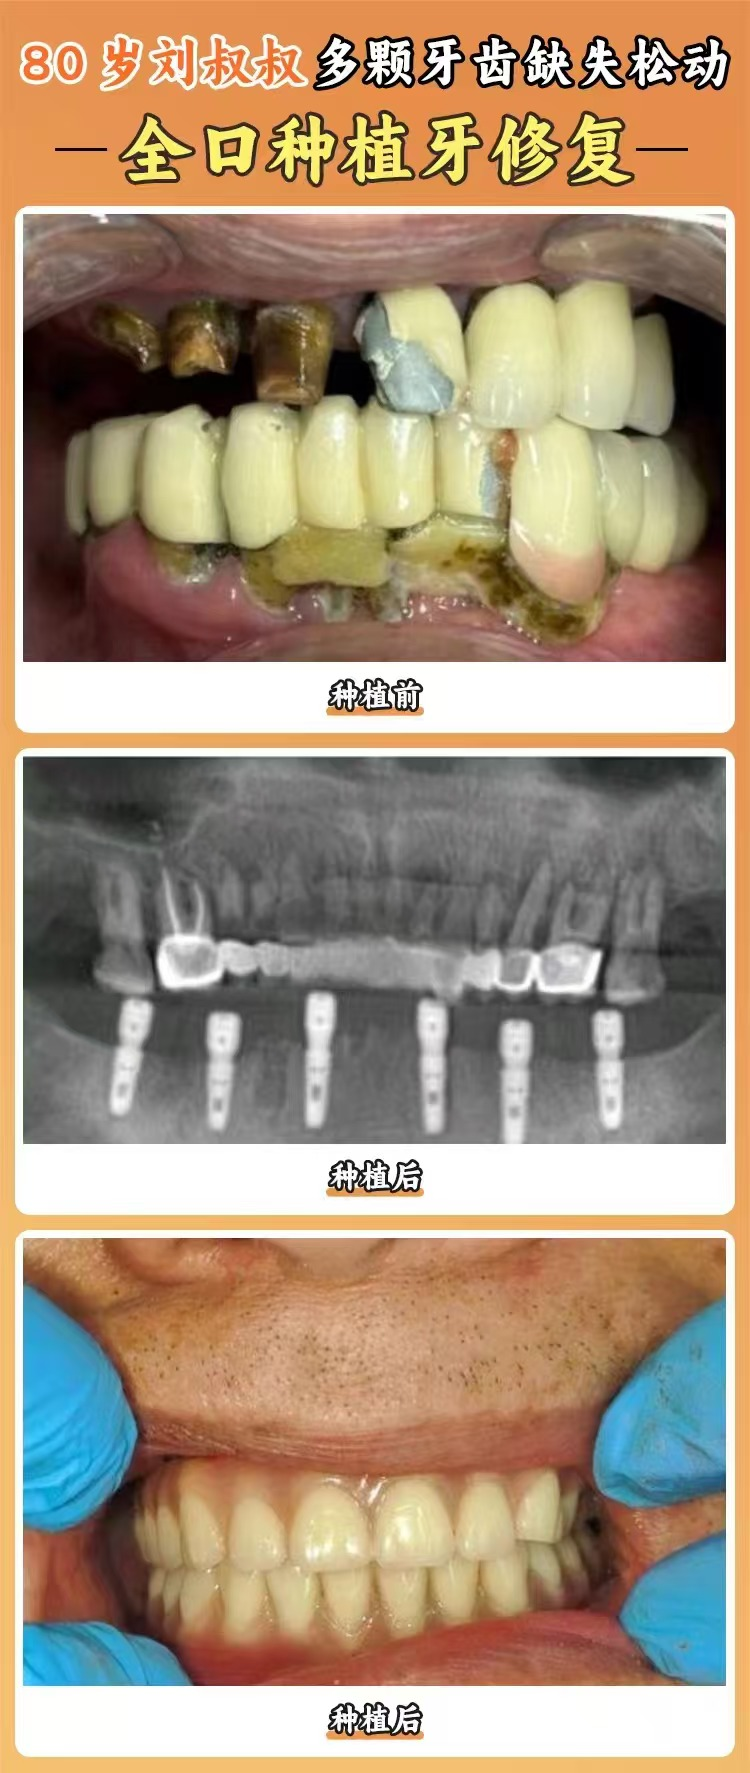

豐富的臨床經(jīng)驗(yàn):曹利娜醫(yī)生在種植領(lǐng)域已經(jīng)積累了多年的臨床經(jīng)驗(yàn),經(jīng)手了眾多種植牙實(shí)例。她熟悉各種口腔情況,能夠根據(jù)患者的不同牙槽骨條件、口腔健康狀況等制定個(gè)性化的種植方案。無(wú)論是簡(jiǎn)單的單顆牙缺失,還是復(fù)雜的多顆牙缺失甚至全口牙缺失,她都能游刃有余地進(jìn)行處理。